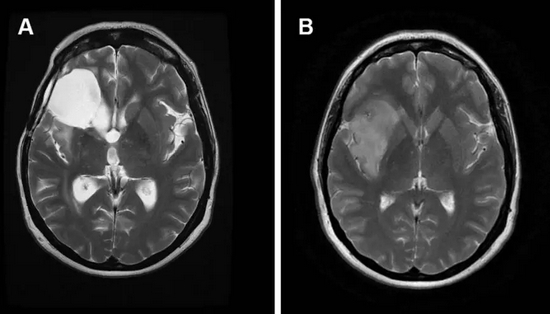

2、颅内占位

脑瘤有良恶性之分,恶性发展快,病程短,神经系统症状逐渐出现,并且进行性加重,带瘤存活 20 余年的可能性微乎其微。

脑胶质瘤

良性发展慢,病程长,患者可以没任何症状,也可以随着肿瘤生长,影响到脑部血液循环,阻塞脑脊液的循环通路,造成颅内积水或脑水肿,甚至会发生脑疝,危及生命。

虽然良性肿瘤存活期可能大于 20 年,但症状应进行性加重,不会以反复发作、不残留神经功能障碍为表现。

同样,我们也不能以华佗想要用斧子砍开头颅进行手术,便断定曹操先生一定就‘脑壳有包’。

脑膜瘤